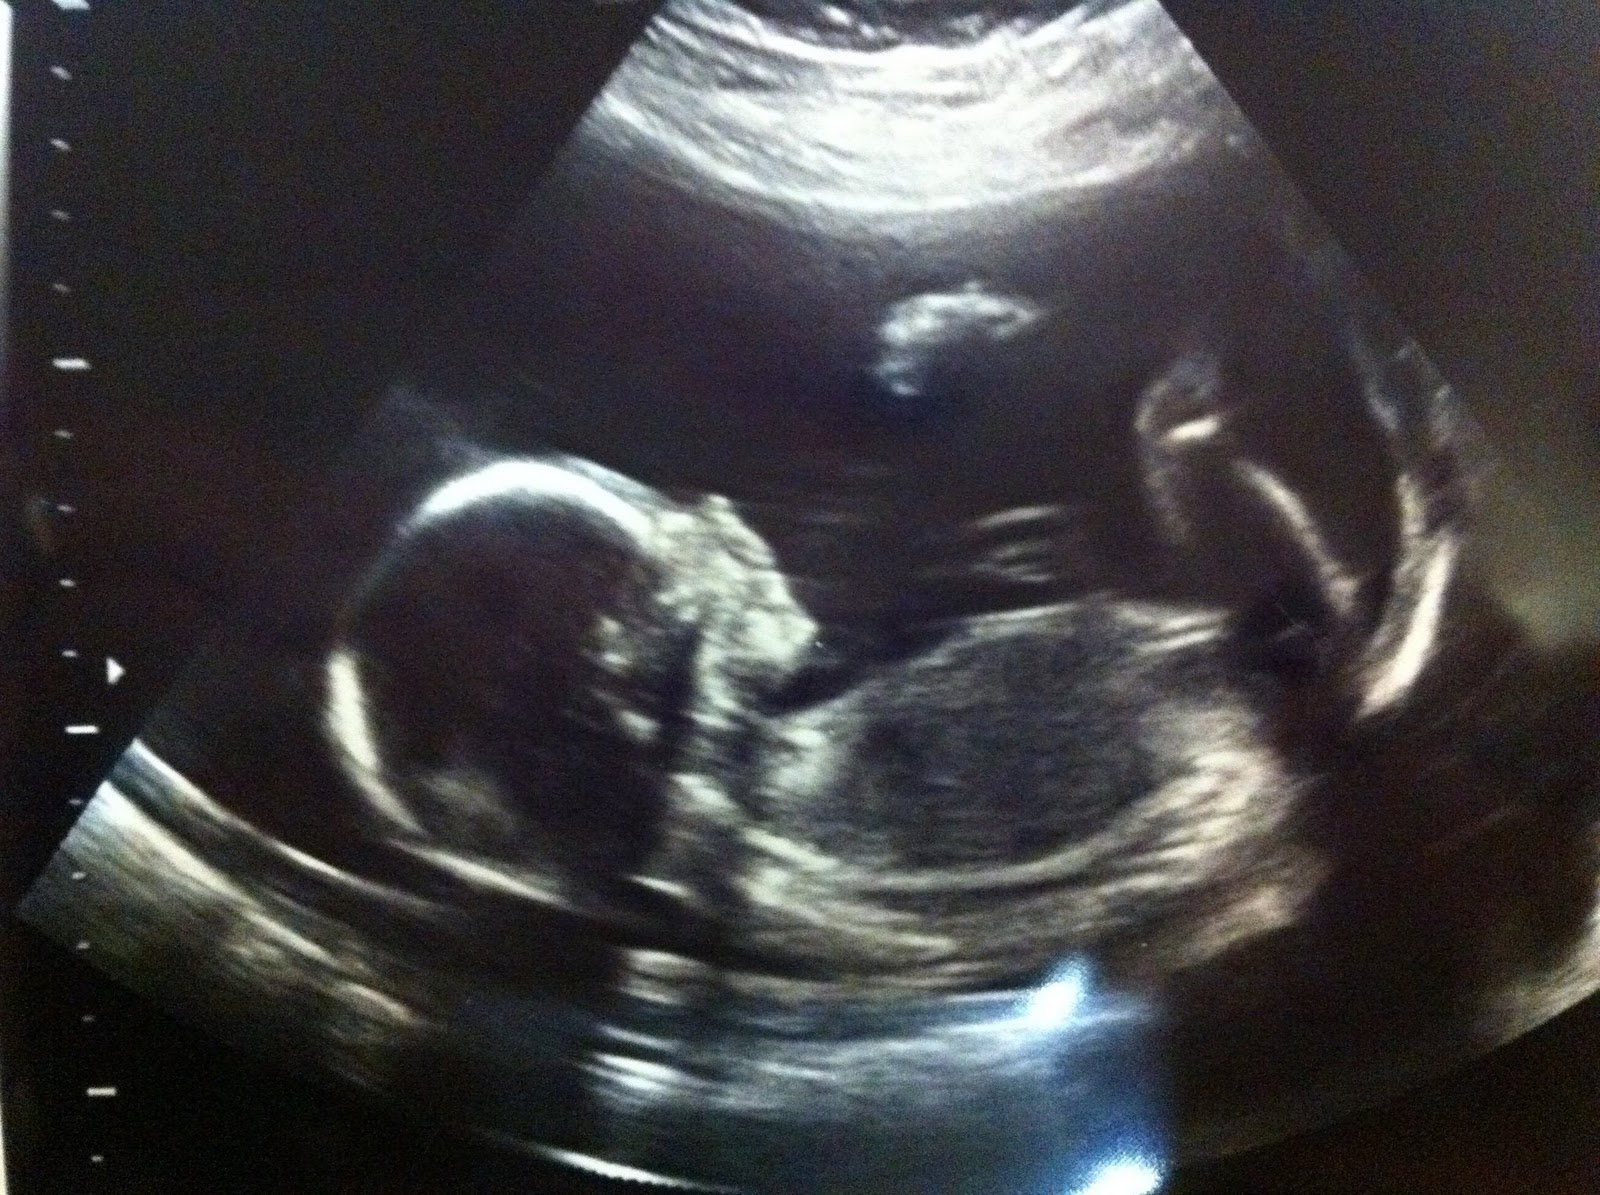

We’re having another boy! May I introduce to you … TWO.

We laughed hysterically after we left the ultrasound room, because ONE is such a boy and he’s such a handful. We can’t imagine having that times two.

Pennie, the goods aren't showing in this picture, but it's VERY obvious when it pops up on the screen!